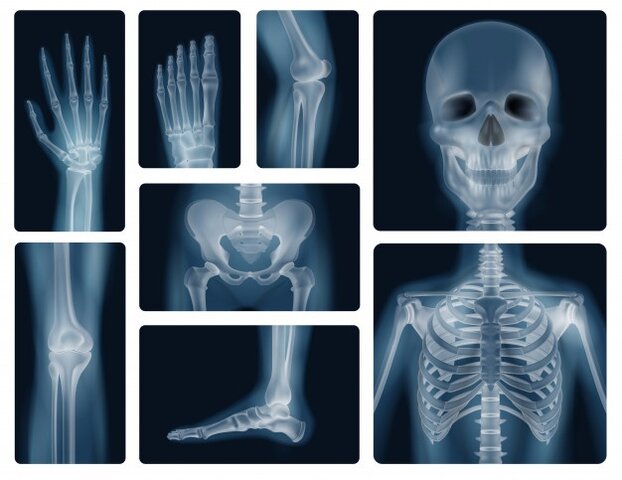

• Magnitudes, unidades y limitación de dosis de radiación utilizadas

Magnitudes, unidades y limitación de dosis de radiación utilizadas

1937, se consideró que una persona sana podía tolerar una exposición profesional a los rayos X y a las radiaciones gamma de hasta 0,2 roentgen por día de trabajo

En 1953, la CIUMR recomendó que en los límites de exposición se tomara en consideración la energía absorbida por los tejidos e introdujo el rad (dosis de radiación absorbida)

En 1964 Se reconoció además el aumento de la radio sensibilidad del feto y se recomendó que las mujeres en edad de procrear no estuvieran expuestas profesionalmente a más de 1,3 rem en un período de 13 semanas

En 1966 expresada en una base anual era de 5 rem para una irradiación uniforme de todo el cuerpo o de las gónadas o la médula ósea roja, que son los tejidos más radiosensibles; 30 rem para la piel, el tiroides y los huesos; 75 rem para las extremidades; y 15 rem para los demás órganos.

La dosis equivalente efectiva establecida para la susceptibilidad a las lesiones de los diferentes tejidos (como se definió en una declaración posterior en 1978). el límite de la dosis efectiva equivalente anual de radiación uniforme era de 5 rem (50 milisievert).